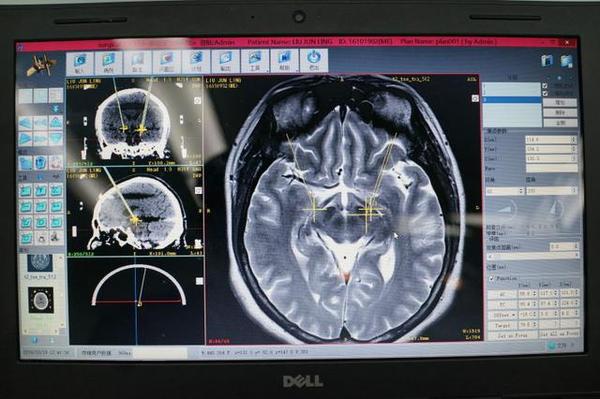

这种手术需要借助于立体定向手术技术,结合相应的成像技术,如功能性核磁共振、脑磁图等。手术过程复杂,手术费用较为昂贵(据说打底30万)。同时,手术的操作过程往往需要经验丰富的治疗团队才能实现。

定位系统

①安装立体定向头架:帮助医师确定放入电极的位置;

②精确定位:通过CT或MRI检查帮助医师获取植入电极定位;

③植入电极:根据定位将电极精准植入大脑刺激部位;

定位系统下植入